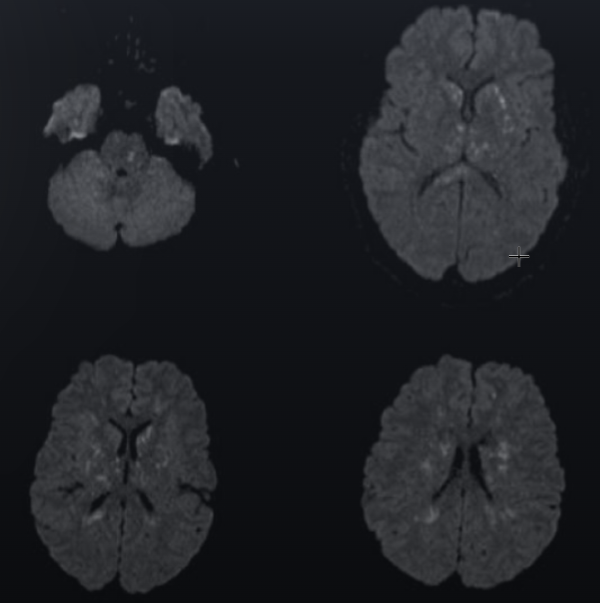

救急外来、31歳女性 発熱、ダルい、胸が苦しい? 指導医「ん~、また肺炎か? B先生、ファーストタッチ頼んだぞ!」 研修医B「は、はいっ!」 —— 10分後 —— B「せ、先生っ!!大変です! ”脂肪塞栓”かもです!!」 指導医「え?脂肪?なんでそんな…」 B「聴診しようと、服をめくったらぁ、 おなかに、むっちゃ青あざがあってぇ… げ!! 見てはいけないものを見てしまったわ~ スルー出来んわ~、と思って聞いたらぁ… 『これ?おととい、脂肪吸引したのよ…』 ふむふむ、DVじゃなくて ほっとしたわ~ ……ん? まてよ? 脂肪吸引→呼吸不全? これってまさか!? 美容外科のホームページで見たことあるぞ! あ~っ! 心エコ―で右心負荷すご! やっぱこれ、脂肪塞栓じゃね?」 (ドキドキ) ——造影CT—— 両側浸潤影あり、血栓塞栓なし →脂肪塞栓症候群! 指導医「観察力えぐい」 —————————